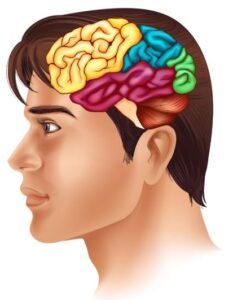

Frontal lobe – is at the front of the brain (yellow section below).

It is responsible for:

- Problem solving

- Planning and organising

- Making judgements

- Emotions, behaviour and mood

- Personality

- Social skills

Parietal lobe – is on the top, back of the brain (blue section below).

It is responsible for:

- Knowing left from right

- Sensations (touch, pressure, temperature, pain)

- Hearing

- Reading

- Smelling

- Tasting

- Touch

- Understanding what we see

- Reading and writing

- Understanding shapes, colour and distance

- Understanding language

- Memory

- Emotions

- Enjoyment of music

- Recognising and identifying things we see (faces or objects)

- Balance

- Coordination

- Movement

- Regulating feelings and responses

- Organising thought

- Breathing

- Swallowing

- Appetite

- Beating of our heart

- Body temperature

- Staying awake or asleep

Lobes

A city is made up of many buildings. A brain has many part too. The main parts of brains are called lobes, each doing different things to help your body to work.